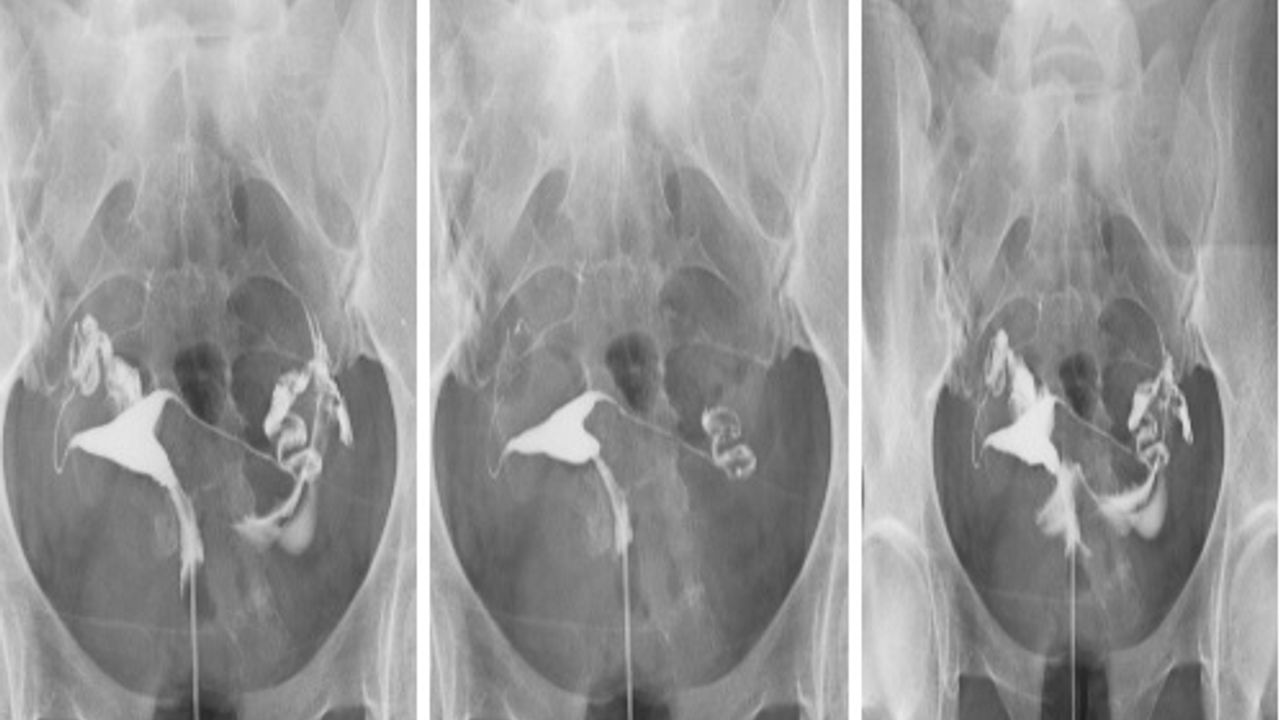

Hastanın rötgen masasına sırt üstü uzanması sağlanır. İlk olarak, muayene spekulumu takılır ve rahim ağzının görüntülenmesi gerçekleşir. Bu adımdan sonra, rahim ağzına doğru ince bir kanül uzatılır. (Kanül: tükenmez kalemin içine benzer ince borucuk) Bu kanül sayesinde, kontrast sıvı rahim içine yavaş yavaş verilir ve röntgen filminin çekilmesi sağlanır.

Kontrast madde tüplere geldiği zaman, hasta hafif bir ağrı hissi duyabilir. Tüplerin açık olması halinde, kontrast madde karın boşluğuna kadar yayılır.

HSG normal olması durumunda, her iki tüp de açık ve rahim içinin şekli normaldir demektir. Rahim içinde bir kitle (miyom veya polip gibi) bulunuyor ise veya tüpler kapalı görünüyorsa, HSG’de bu durum anormal bir görüntü oluşturur.

Burada önemli olan bir nokta, HSG’de tüplerin açık izlenmesi, kapalı izlenmesine göre daha güvenilir bir bilgidir. Bunun sebebi ise, HSG’de tüpler çekim sırasında kasılarak (spazm) kapalı gibi görünebilmektedir. Kısacası, HSG’de kapalı izlenen tüp, asıl itibari ile açık olabilir. Bunun anlamak için ise laparoskopi yapılarak tüplerin detaylı bir şekilde incelenip değerlendirilmesi gerekir.